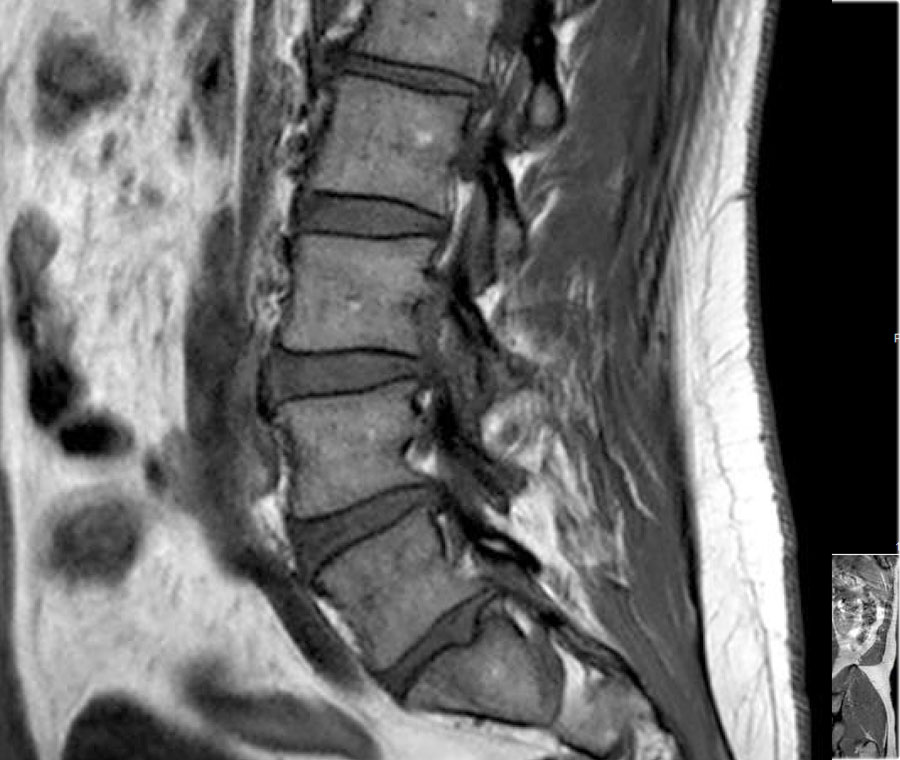

Trước tiên hãy quan sát các hình ảnh.

Nhấp để phóng to.

Sau đó tiếp tục đọc.

Các dấu hiệu bao gồm:

- Thoát vị đĩa đệm L3L4.

- Di trú lên phía trên.

- Chèn ép rễ thần kinh L3 trong lỗ liên hợp.

Cường độ tín hiệu của thoát vị đĩa đệm trên chuỗi xung T1W thường ở mức trung gian, trong khi trên chuỗi xung T2W có thể tăng tín hiệu trong trường hợp nhân nhầy thoát vị mới hoặc giảm tín hiệu trong trường hợp thoát vị cũ hơn.

Hình ảnh thoát vị tăng tín hiệu (mũi tên vàng trên ảnh cắt ngang) trượt qua vết rách vòng sợi và chèn ép rễ thần kinh L5 bên trái (mũi tên xanh dương).